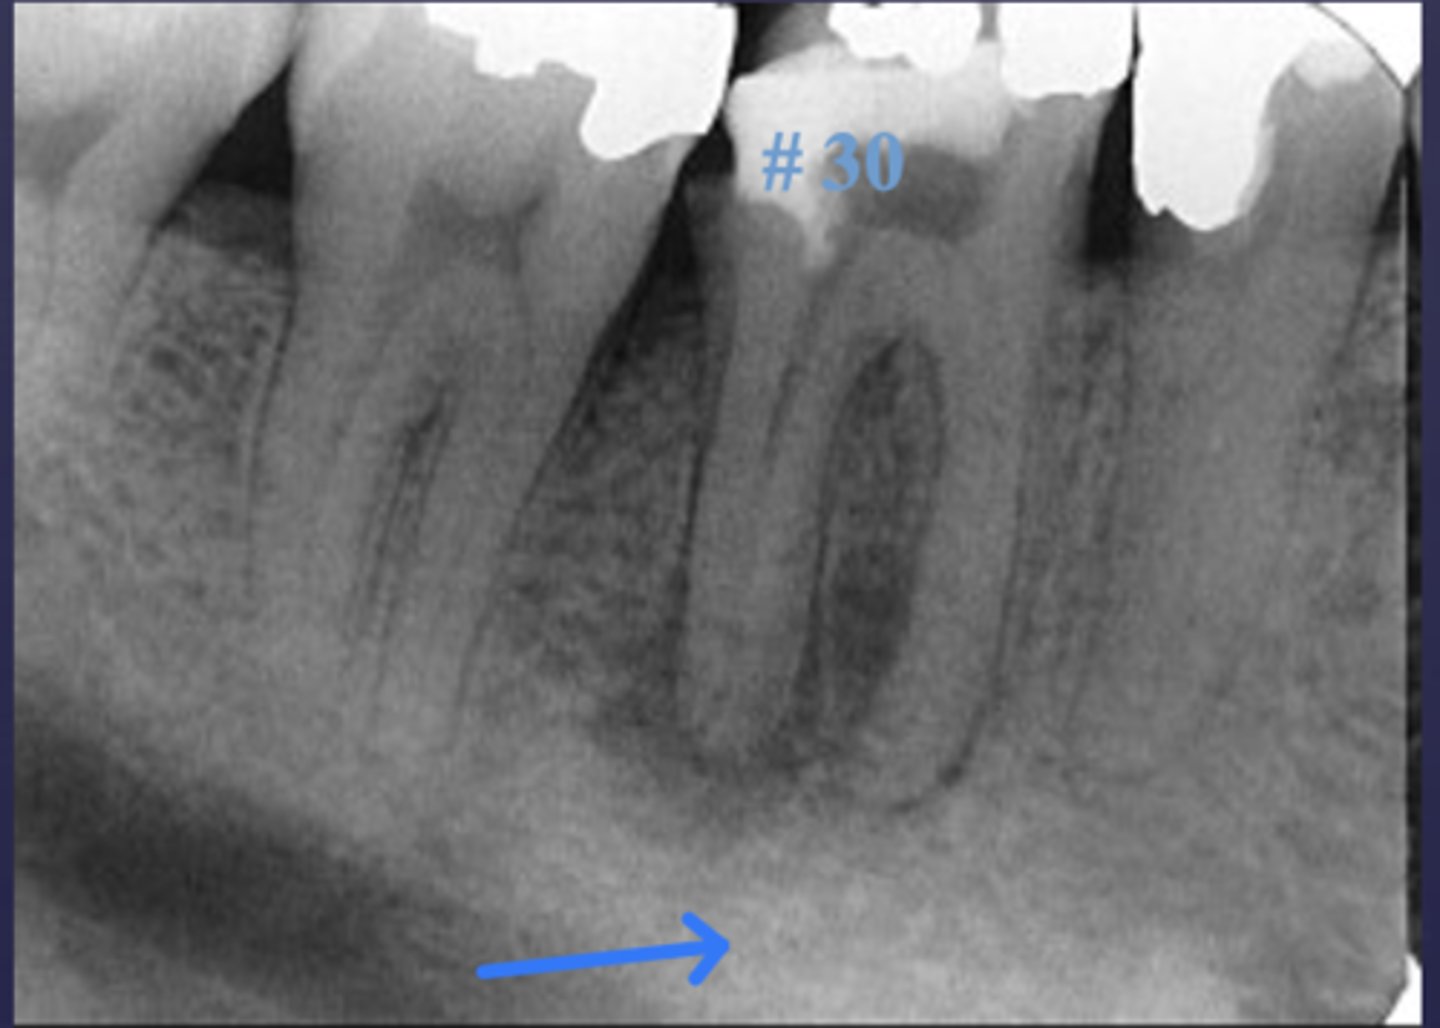

These arrows are pointing at what?

moth-eaten appearance of acute osteomyelitis

The moth eaten appearance is associated with what?

acute osteomyelitis, mixed radiolucent/radiopaque areas